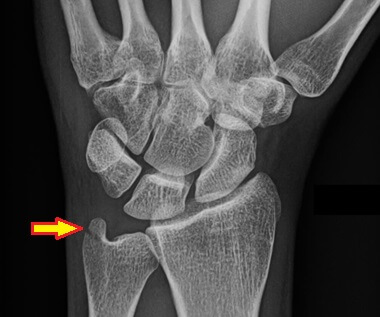

An ulnar styloid fracture occurs when the tip of the ulna (inner wrist bone) breaks, usually from a fall onto an outstretched hand.

Common symptoms include inner wrist pain, swelling, bruising and tenderness and there may be a visible deformity.

Minor cases can be treated in a cast/splint but more severe injuries require surgery, especially if there are other associated injuries. FIND OUT MORE >